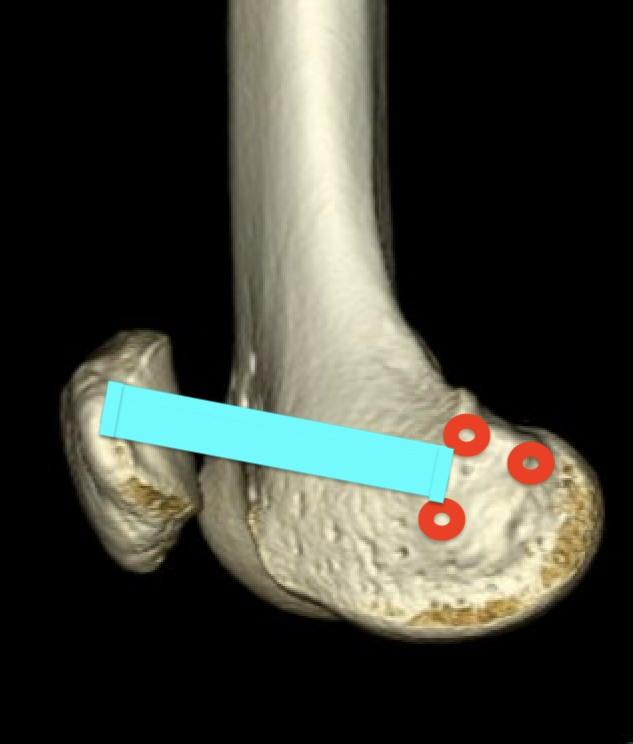

Origin

- medial femoral condyle

- between medial femoral epicondyle and adductor tubercle

- superior to origin of MCL